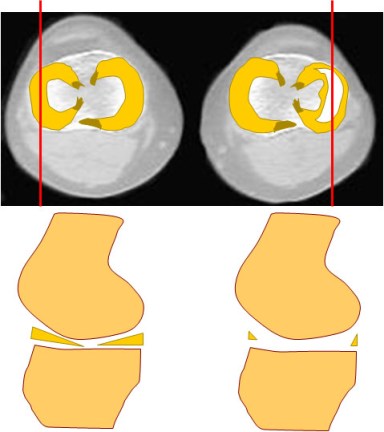

SIGNO DE LA PAJARITA AUSENTE

En los cortes sagitales de resonancia magnética de la rodilla, el cuerpo del menisco normal se parece a una pajarita (o corbata de lazo), es decir, se ven dos triángulos que apuntan uno al otro y se unen en el centro. Con cortes de 5 mm, debe verse en dos cortes consecutivos.

El signo de la pajarita ausente consiste en que el cuerpo del menisco es visible en menos de dos cortes consecutivos. Esto indica que existe una rotura longitudinal del cuerpo meniscal con desplazamiento del fragmento interno (rotura «en asa de cubo»).

Arriba a la izquierda: plano axial que muestra los meniscos normales. Arriba a la derecha: esquema de una rotura en “asa de cubo” del menisco externo. Las líneas rojas representan los planos de corte coronal.

Abajo a la izquierda: esquema del corte coronal en el menisco normal en el que se ve la imagen de pajarita. Abajo a la derecha: el signo de la pajarita ausente en la rotura meniscal.